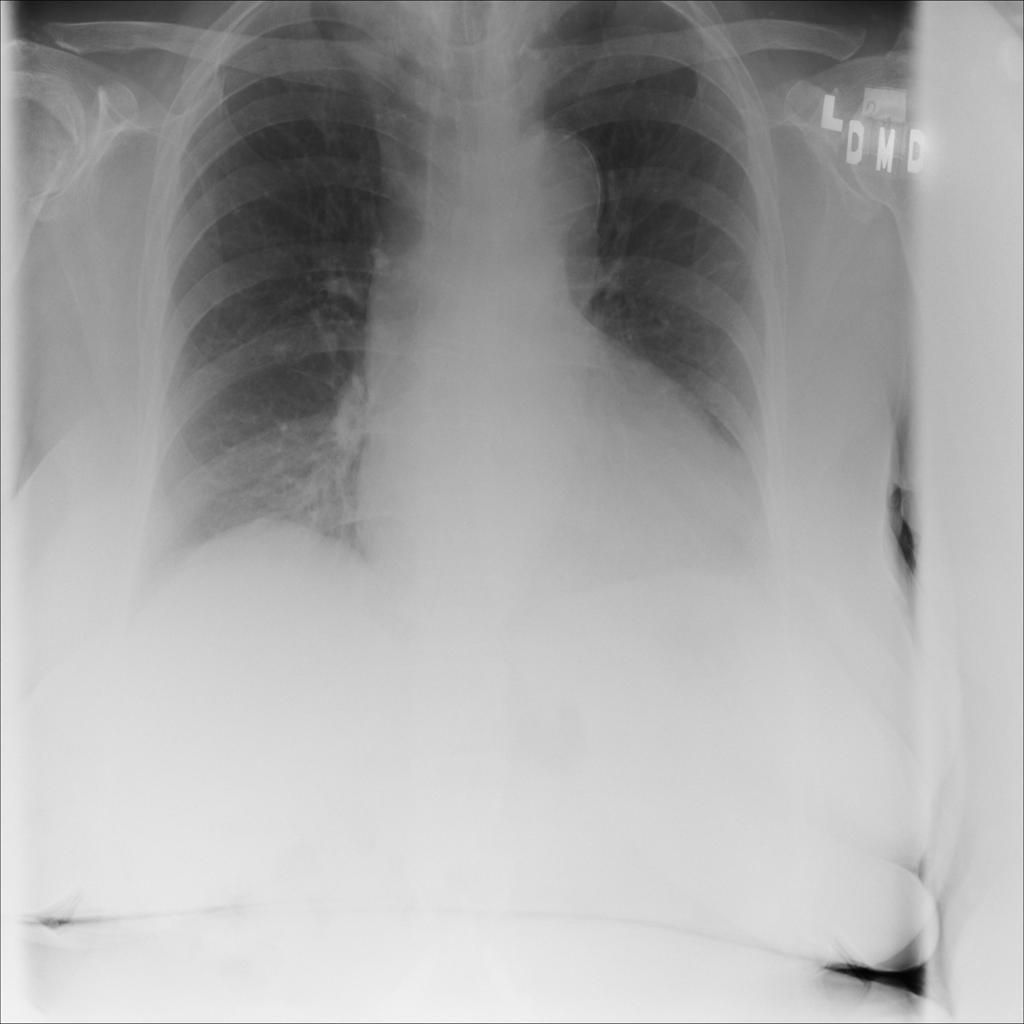

Showing up to 90 reference images for Cardiomegaly.

PAT-3384 · IMG-000Cardiomegaly

PAT-3384 · IMG-000

AP